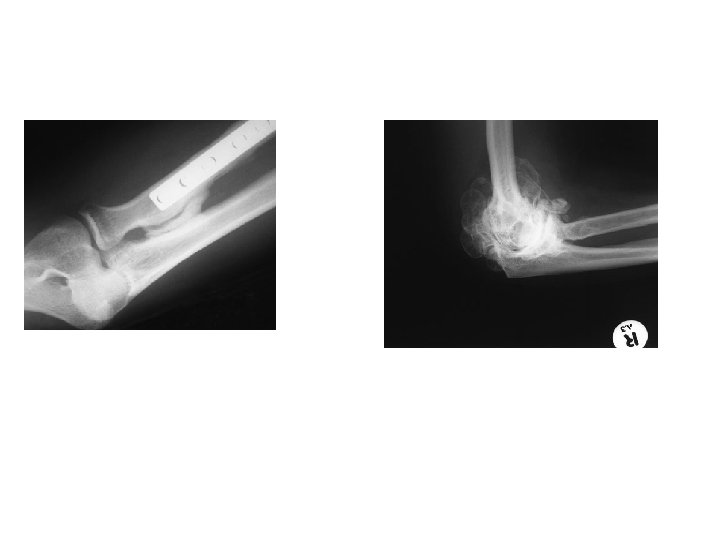

POST-TRAUMATIC STIFFNESS • the elbow is particularly prone to posttraumatic stiffness. The more obvious causes (as with other joints) are either: 1 -extrinsic (e. g. soft-tissue contracture or heterotopic bone formation). 2 - intrinsic (e. g. intra-articular adhesions and articular incongruity), or a combination of these.

OPERATIVE TREATMENT • The indication for operative treatment is failure to regain a functional range of movement at 12 months after injury. • If there is heterotopic ossification, it is important to wait until the bone is ‘mature’, i. e. showing clear cortical margins and trabecular markings on x-ray. There is no point in a soft tissue release if the x-ray or CT shows that bone incongruity is blocking movement.

• The objectives are determined by the type of Pathology: 1 -Heterotopic bone can be excised, 2 -Capsularrelease or capsulectomy (open or arthroscopic) may restore a satisfactory range of movement. 3 -Intra-articular procedures include fixing of ununited fractures or correction of malunited fractures.

• Post-traumatic radio-ulnar synostosis sometimes follows internal fixation of fractures of the radius and ulna. It is treated by resection when the synostosis has matured (this takes about one year) followed by diligent physiotherapy.